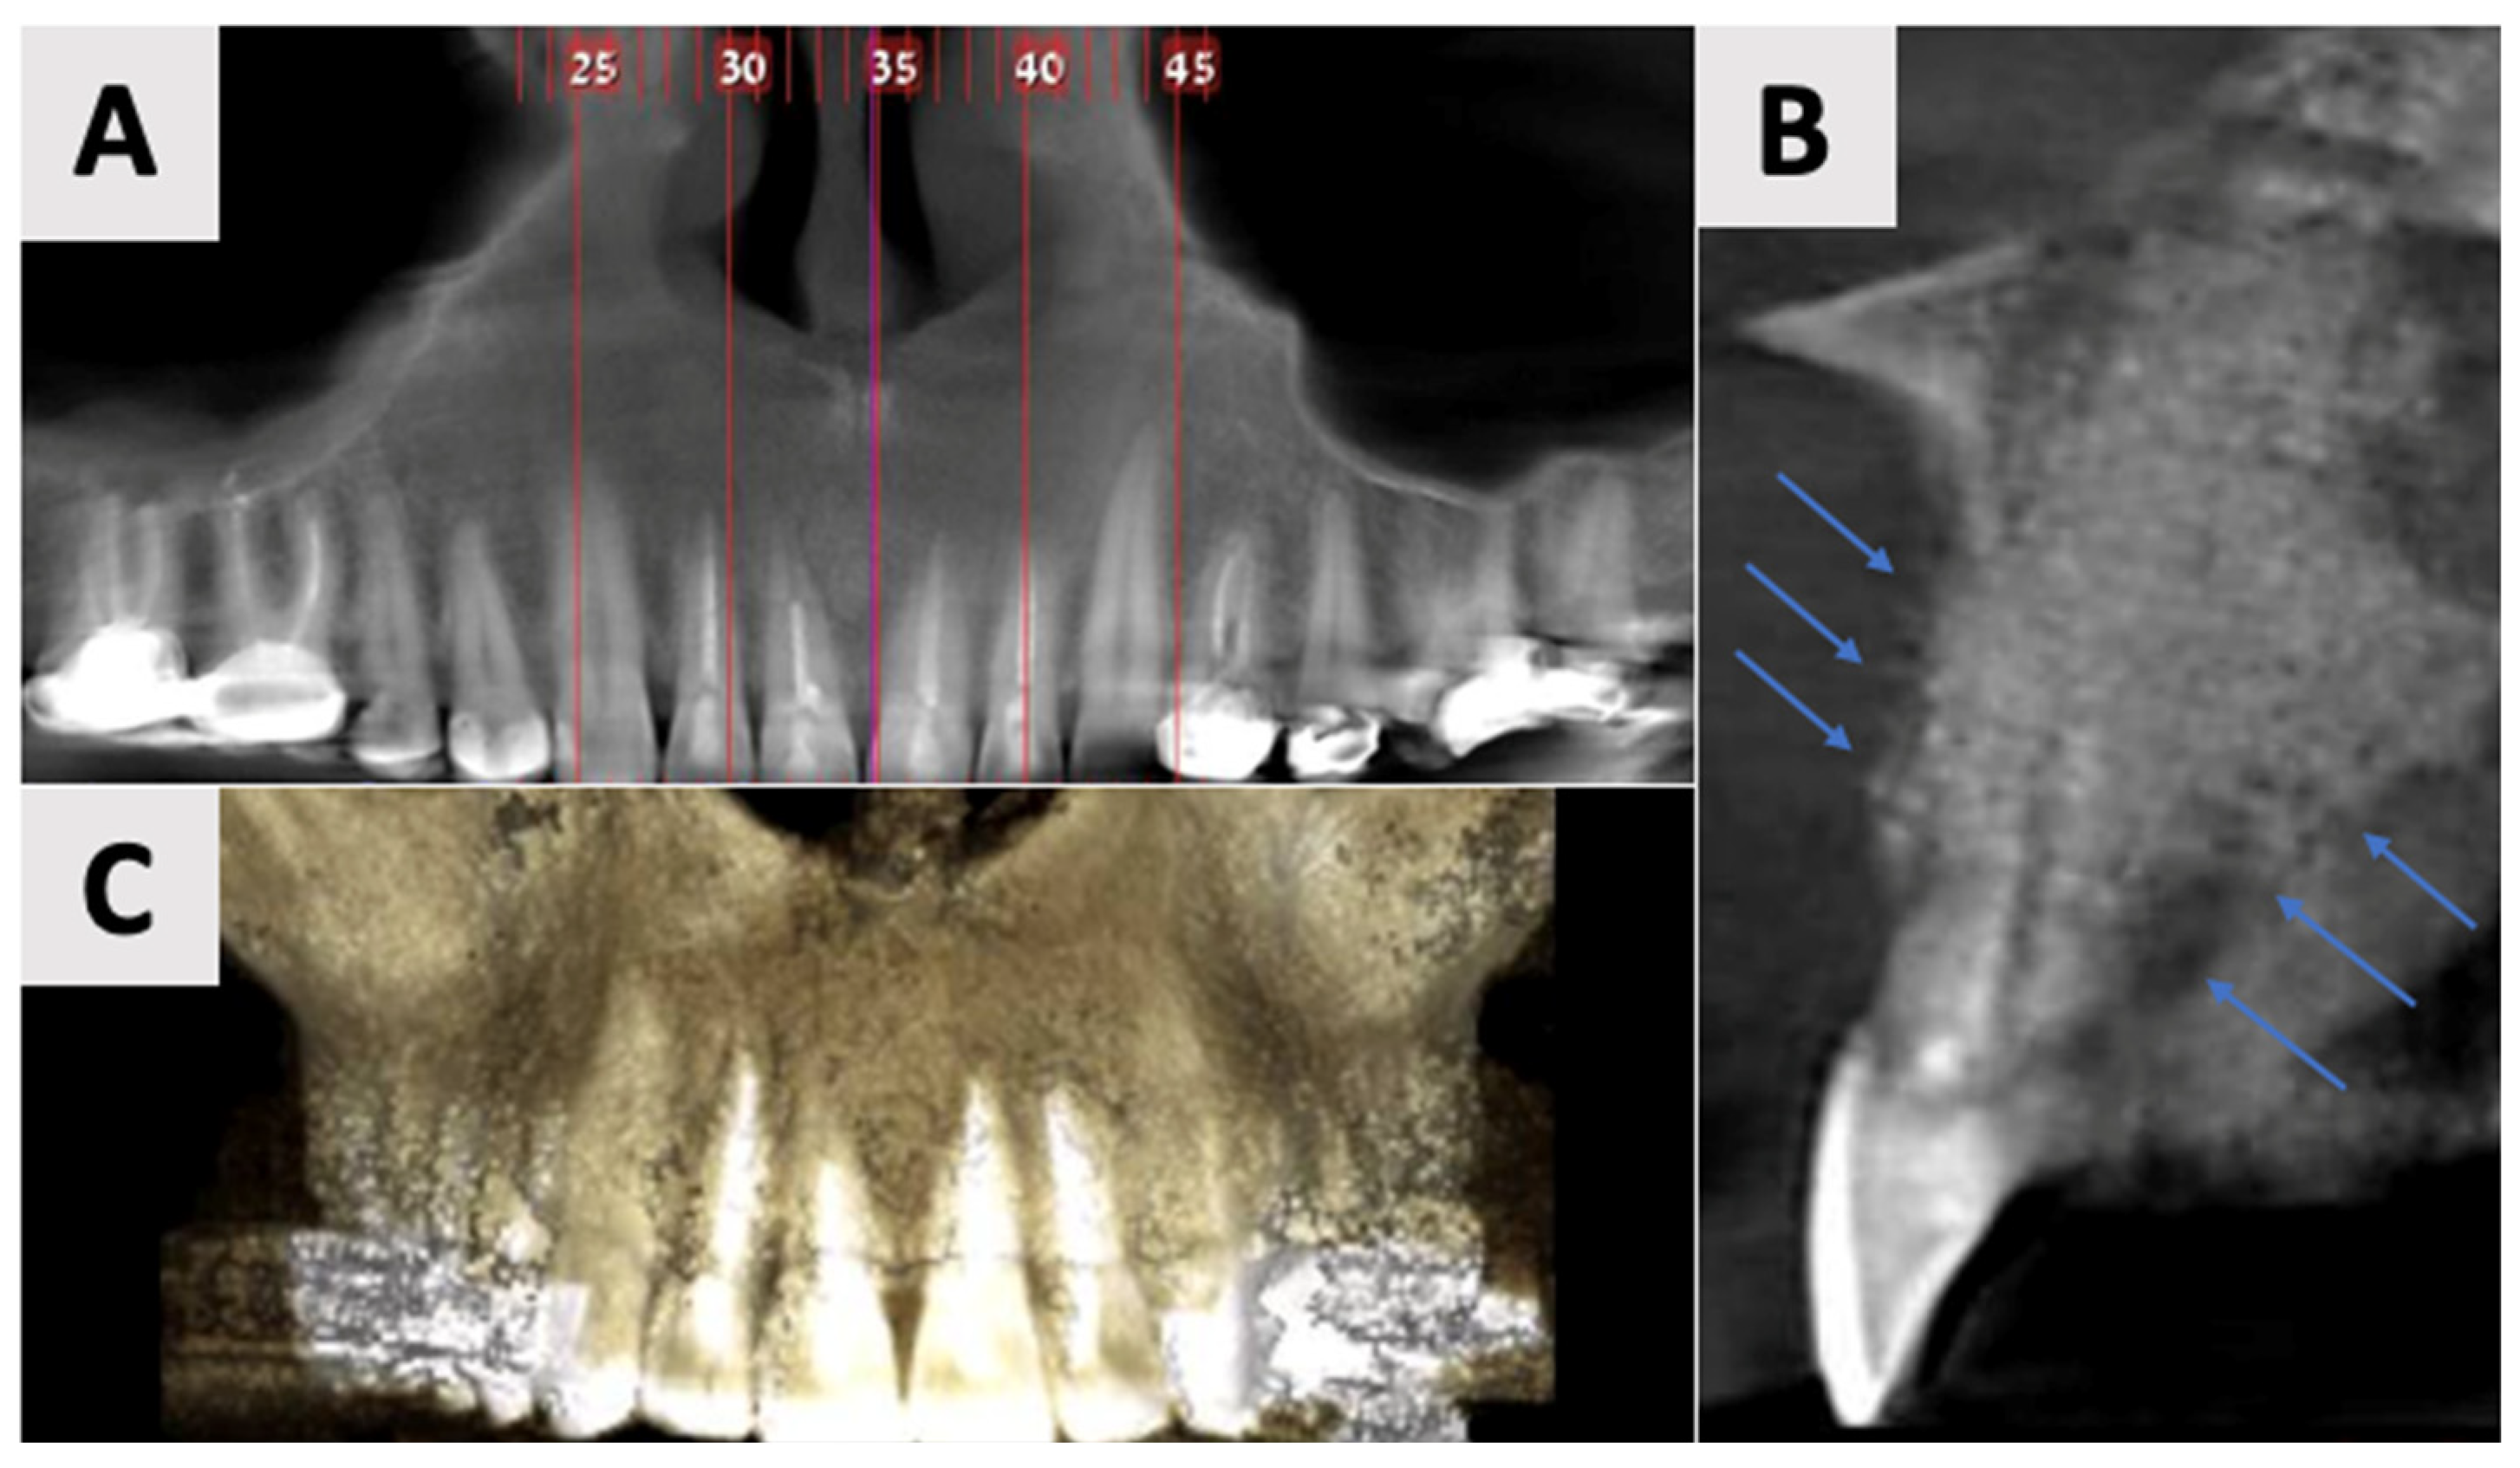

Figure 2.

Radiographic evaluation of cyst six months following marsupialization. (A) Panoramic reconstruction illustrating the initial defect site prior to enucleation. (B) Cyst regression and improved bone density in the affected area. (C) Paraxial view.

The findings indicated favorable cyst regression and improved bone density in the affected area. Based on these results, it was determined that the marsupialization had created optimal conditions for the next phase of treatment. Consequently, the decision was made to proceed with cyst enucleation, marking the transition to the definitive surgical management of the lesion.